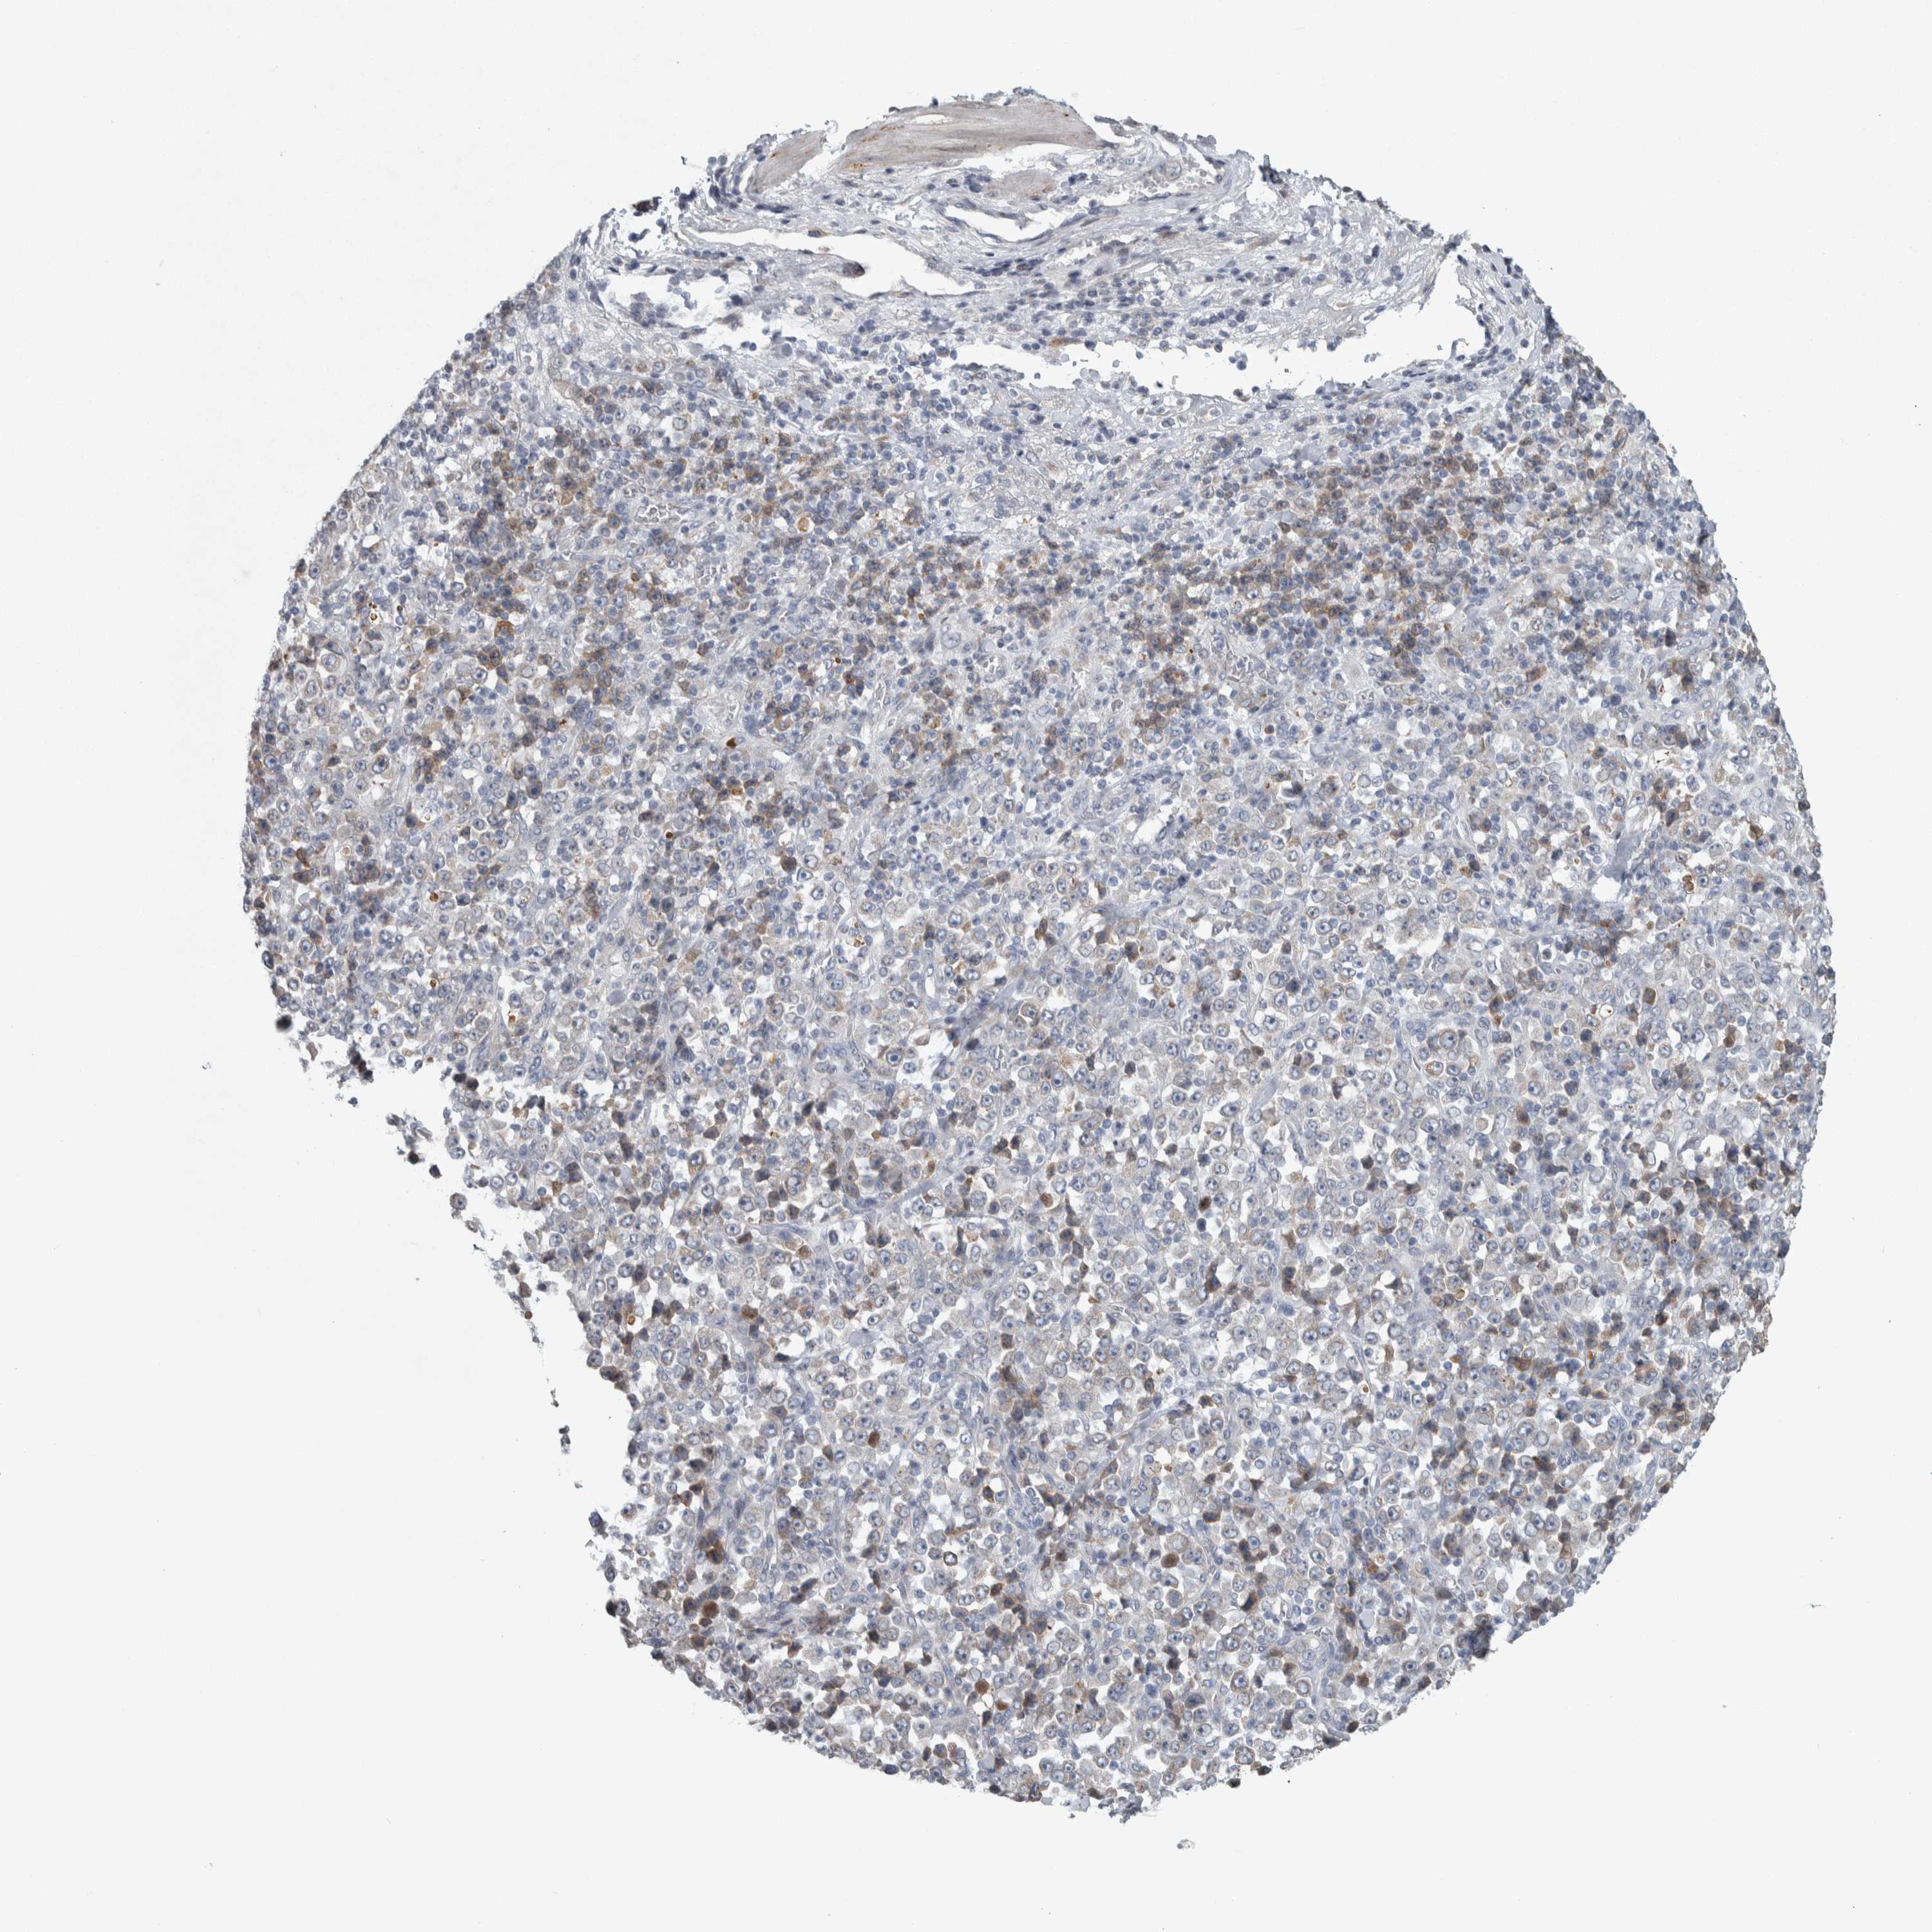

STOMACH CANCER - Protein expressioni

A mouse-over function shows sample information and annotation data. Click on an image to view it in a full screen mode. Samples can be filtered based on level of antibody staining by selecting one or several of the following categories: high, medium, low and not detected. The assay and annotation is described here.

Note that samples used for immunohistochemistry by the Human Protein Atlas do not correspond to samples in the TCGA dataset.

Antibody stainingi

Antibody staining in the annotated cell types in the current human tissue is reported as not detected, low, medium, or high, based on conventional immunohistochemistry profiling in selected tissues. This score is based on the combination of the staining intensity and fraction of stained cells.

Each image is clickable and will lead to virtual microscopy that enables deeper exploration of all samples and also displays staining intensity scores, fraction scores and subcellular localization as well as patient and tissue information for each sample.

Antibody HPA018002

Antibody HPA024071

Antibody CAB013470

Staining

High

Medium

Low

Not detected

Intensity

Strong

Moderate

Weak

Negative

Quantity

>75%

75%-25%

<25%

None

Location

Nuclear

Cytoplasmic/membranous

Cytoplasmic/membranous,nuclear

Adenocarcinoma, NOS

Adenocarcinoma, High grade